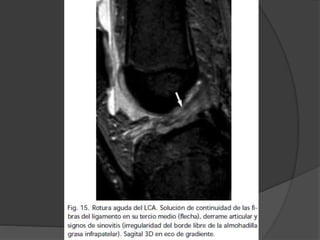

LCA

 Rotura completa:

 Mas frecuentes en el extremo

proximal , difícil de visualizar en

sagitales por efecto de volumen

parcial con la cortical del cóndilo

externo. = axiales y cor.

 En las roturas intersticiales se

observa el ligamento engrosado e

hiperintenso.

LCA  Rotura completa: Mas frecuentes en el extremo proximal , difícil de visualizar en sagitales por efecto de volumen parcial con la cortical del cóndilo externo. = axiales y cor.  En las roturas intersticiales se observa el ligamento engrosado e hiperintenso.  La avulsión distal = niños porque el ligamento es más resistente que el hueso inmaduro. Es importante precisar el tamaño y grado de desplazamiento del fragmento óseo

LCA  Roturas crónicas no hay edema ni sinovitis  pequeño derrame articular.  LCA no se ve en sagital o coronal por estar retraído  LCA puede encontrarse adherido al LCP falseando el test del cajón anterior.  La tibia aparece desplazada anteriormente respecto al fémur  Signo indirecto de rotura del LCA: el aumento de la curvatura o redundancia del LCP.